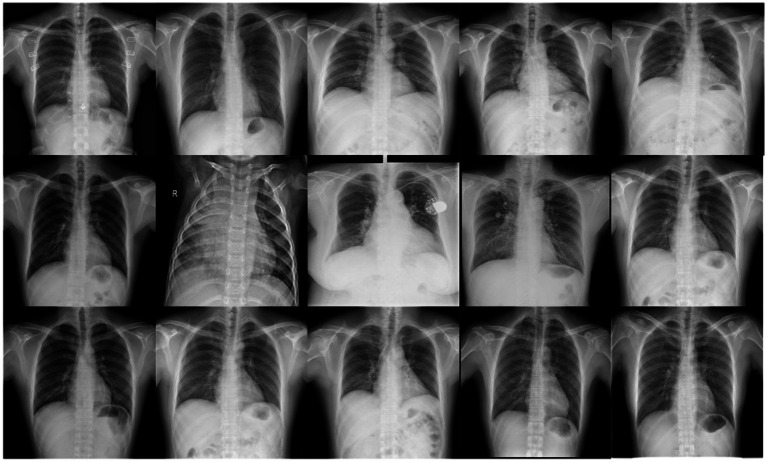

Early and accurate diagnosis of pneumonia is crucial to improve cure rates and reduce mortality. Traditional chest X-ray analysis relies on physician experience, which can lead to subjectivity and misdiagnosis. To address this, we propose a novel pneumonia diagnosis method using the Fast-YOLO deep learning network that we introduced. First, we constructed a pneumonia dataset containing five categories and applied image enhancement techniques to increase data diversity and improve the model's generalization ability. Next, the YOLOv11 network structure was redesigned to accommodate the complex features of pneumonia X-ray images. By integrating the C3k2 module, DCNv2, and DynamicConv, the Fast-YOLO network effectively enhanced feature representation and reduced computational complexity (FPS increased from 53 to 120). Experimental results subsequently show that our method outperforms other commonly used detection models in terms of accuracy, recall, and mAP, offering better real-time detection capability and clinical application potential.

Abstract Image